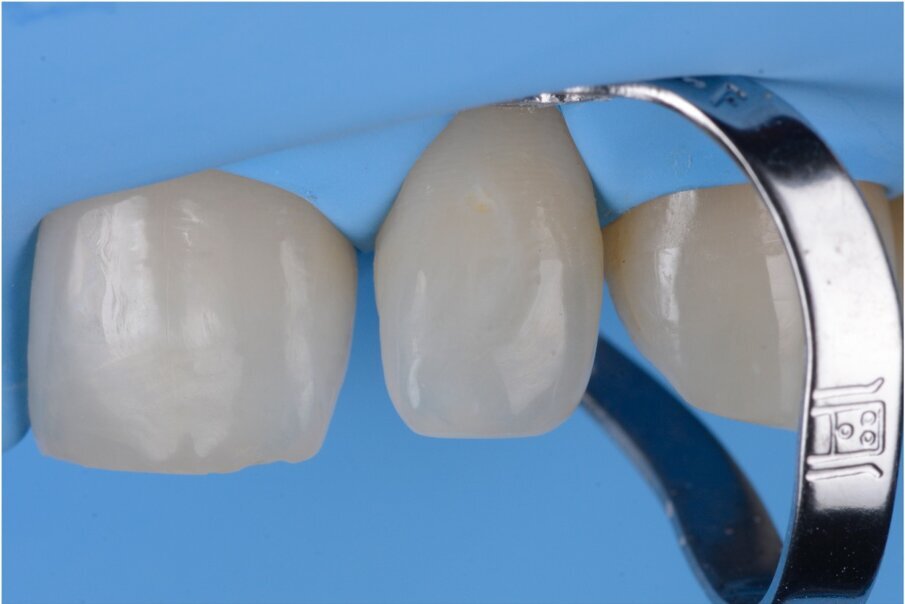

Fig. 2–4: Common troubles with a classic approach.

Fig. 3

Fig. 4

What were the associated problems with the older techniques including the one you used? The greatest problem for the freehand techniques, without a doubt, is the lack of cervical precision and the creation of overhangs. I have seen countless patients with bleeding gums that are not able to floss properly. Another common problem with the classical approach was the final shape. With a double emergence profile, it gave the final restoration an awkward shape (Figs. 2–4). Problems for direct diastema closure exclusively with matrices are the over contouring and the under contouring at the cervical level, discordant contact points, shifted proximal contacts, and massive excess production. To be honest, I have always been discouraged from trying that approach.